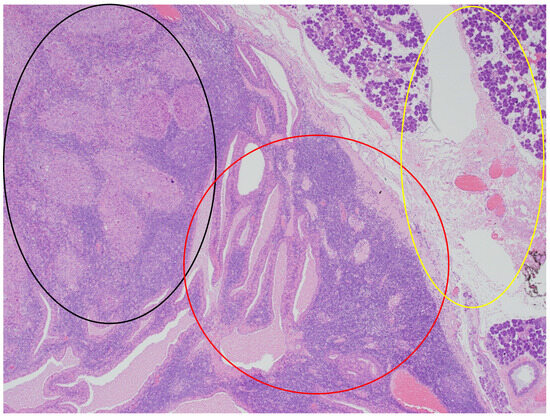

Figure 4.

The parotid Warthin tumor, with the benign epithelial cystic component in the central and right parts of the photo (red circle), with the rim of parotid gland tissue not involved in any neoplasm on the right (yellow circle), and the squamous cell carcinoma metastasis in the superior left part (black circle). HE staining. Magn. ×88.